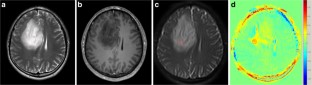

Fig. 2